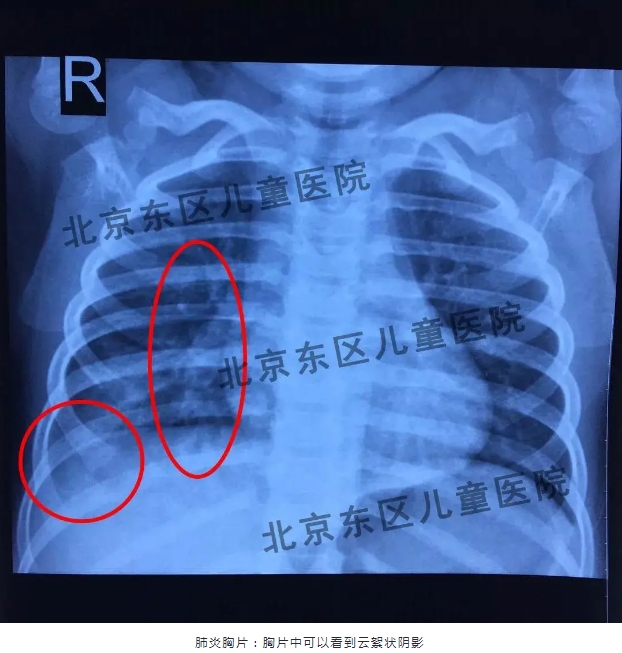

从目前临床来看,今年的肺炎支原体较去年相比还是有些变化的,今年的特点主要表现为孩子的症状不典型,有些孩子既发烧又咳嗽;有些孩子是只高烧,但是一开始不咳嗽,在3-4天后才出现咳嗽的表现。还有些孩子听着肺里也没事儿,咳嗽3天,也不发烧,一拍片子已经是肺炎了,所以很多家长都不太理解,这主要是因为支原体肺炎早期病变是在肺间质,所以往往听诊听不到啰音,但并不代表孩子没有肺炎。所以提醒家长们要注意如果孩子持续发烧超过三天,不管有没有咳嗽或者只是剧烈的咳嗽,不发烧的情况,一定要去医院请医生评估一下是感冒、支气管炎还是肺炎,千万不要在家扛着,以免延误病情。

肺炎听得见、看得见吗?

很多家长可能遇到过这种情况:孩子发烧咳嗽到医院看病,医生听诊后说肺部没什么问题,但是过了几天病情没有好转再到医院检查就变成肺炎了,家长就对医生的听诊水平产生了质疑。